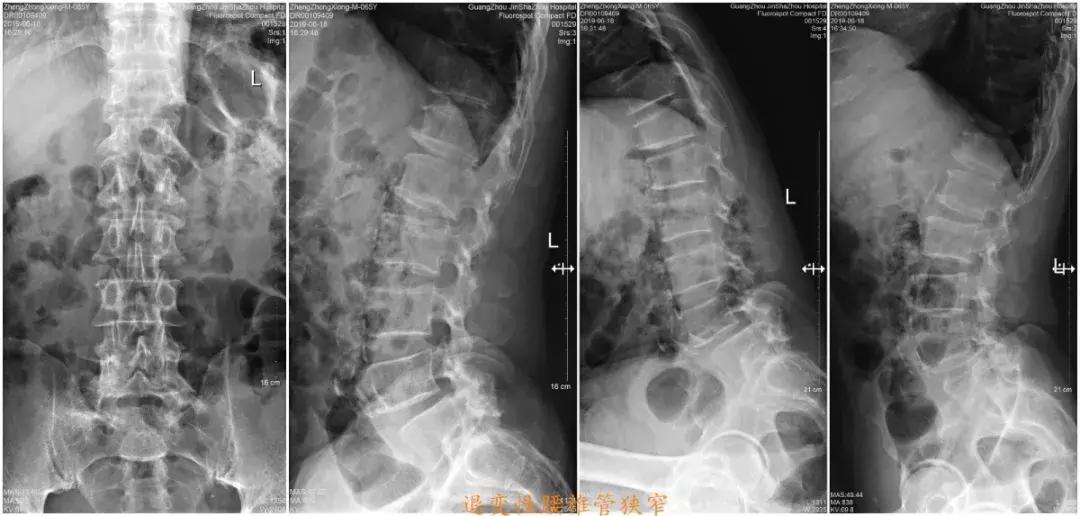

影像学检查